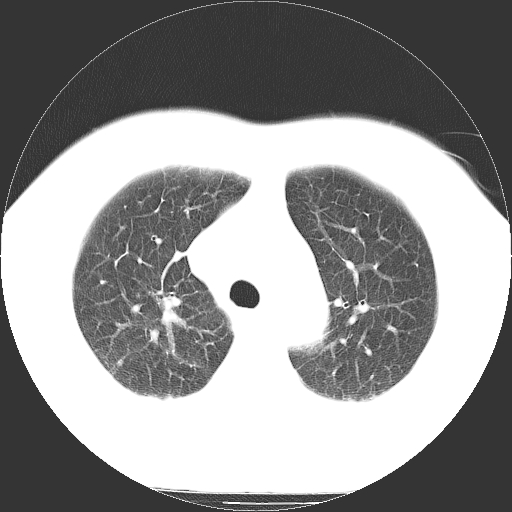

男,65岁,咳嗽、咳痰、发热5天。

慢支 肺间质纤维化合并感染!

支气管扩张合并感染,胸膜肥厚

考虑慢支并感染,肺间质纤维化。

两肺间质性炎症并感染

慢支,肺心病

支持慢性支气管炎伴感染,双侧少量胸腔积液.

两肺间质纤维化,支扩合并感染,双侧胸腔积液

感染,肺间质纤维化。

慢支 肺间质纤维化合并感染

支持慢性支气管、肺间质纤维化合并感染。

慢性支气管炎并感染,支扩,双侧少量胸腔积液.